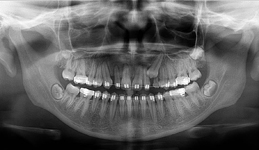

Lékař si vytvoří všechny typy zobrazení potřebných pro naplánování – tedy 2D snímky (panoramatický), příčné řezy i 3D model.

Vidí zde i důležité anatomické útvary – čelistní dutinu, průběh nervu atd. Po proměření množství kosti – šířky i výšky vybere z databáze vhodný typ implantátu a umístí ho do požadované lokality.

Ihned vidí jeho pozici ve všech 3 rovinách a na všech snímcích i 3D modelu. Může upravovat podle potřeby jeho pozici, sklon atd.

Všechny vybrané a správně umístěné simulované implantáty se ukládají do „počítačové karty“ pacienta s jejich pozicí, délkou, průměrem, typem i sklonem.

Lékař i pacient tedy ještě před vlastní operací vidí, jak by mělo ošetření probíhat a vypadat.